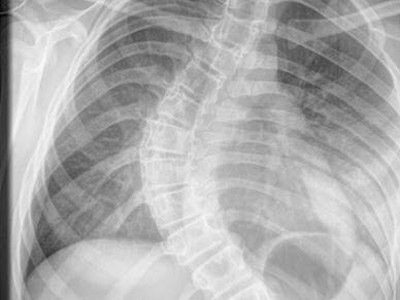

| Ảnh chụp X-quang xương sống của Ellen. |

Ellen Wagstaff bắt đầu cảm thấy đau lưng vào tháng 4-2010. Sau đó, Ellen đã được đưa tới bệnh viện để khám. Kết quả kiểm tra cho thấy bé gái 12 tuổi này bị mắc chứng bệnh vẹo xương sống tự phát rất hiếm gặp. Lúc đó, độ vẹo xương sống của Ellen là 60 độ. Hiện tại, xương sống của cô bé bị vẹo một góc 90 độ.